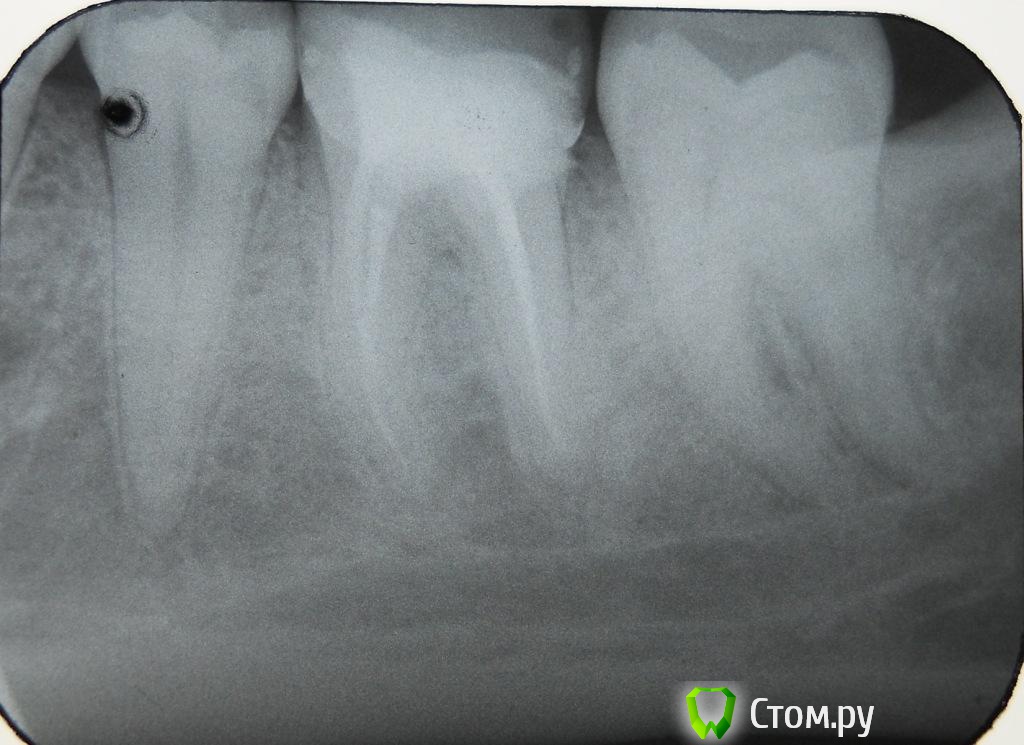

Aalsol Опубликовано 3 июня, 2014 Автор Поделиться Опубликовано 3 июня, 2014 может эти получше. У меня к сожалению есть негатив только. цифрового снимка нет((( Ссылка на комментарий

red_butler Опубликовано 4 июня, 2014 Поделиться Опубликовано 4 июня, 2014 Если судить, только по снимку - зуб можно вылечить, сходите на консультацию к стоматологу-эндодонтисту Ссылка на комментарий

Aalsol Опубликовано 4 июня, 2014 Автор Поделиться Опубликовано 4 июня, 2014 (изменено) А трещина которая в корень уходит влияет как то на решение?И не могли бы вы описать в кратце алгоритм лечения? чтобы понимать о чем говорить и что предлогать доктору?вот еще попробывал переснять снимок Изменено 4 июня, 2014 пользователем Aalsol Ссылка на комментарий

DokDent Опубликовано 4 июня, 2014 Поделиться Опубликовано 4 июня, 2014 Как раз он и говорит что надо удалять. Мы начали делать коронку на него. Сейчас стоит временная. Ну и вот в это воскресенье зуб заболел. Как я писал выше на десне появилось уплотнеие! Но боль вся прошла! Ну раз он заболел - он сказал надо удалять - толку не будет ((((( типа или через трещинку попадает микробы. Или на корне как он говорит воспалилась гранулема. К сож я снимки не понимаю и ни чего не могу сказать есть гранулема или нет!Проблема не в гранулёме. Проблема в трещине. Как она проходит и где заканчивается по Вашему снимку не видно (На рвг определяется далеко не всегда). Возможен перелом и с коронкой. Исчезновение боли не показатель благополучного исхода. Ссылка на комментарий

red_butler Опубликовано 5 июня, 2014 Поделиться Опубликовано 5 июня, 2014 Спасибо! Но всетаки если лечение, то что оно должно предусматривать? Каков план?И почему тогда доктор настаивает на удалении? Не предлагая полечить?нам приходится отвечать, опираясь только на снимок не совсем хорошего качества. Нужен очный осмотр, возможно план будет понятен только после удаления пломбы и/или компьютерной томограммы. Сходите еще на консультацию к другим врачам Ссылка на комментарий